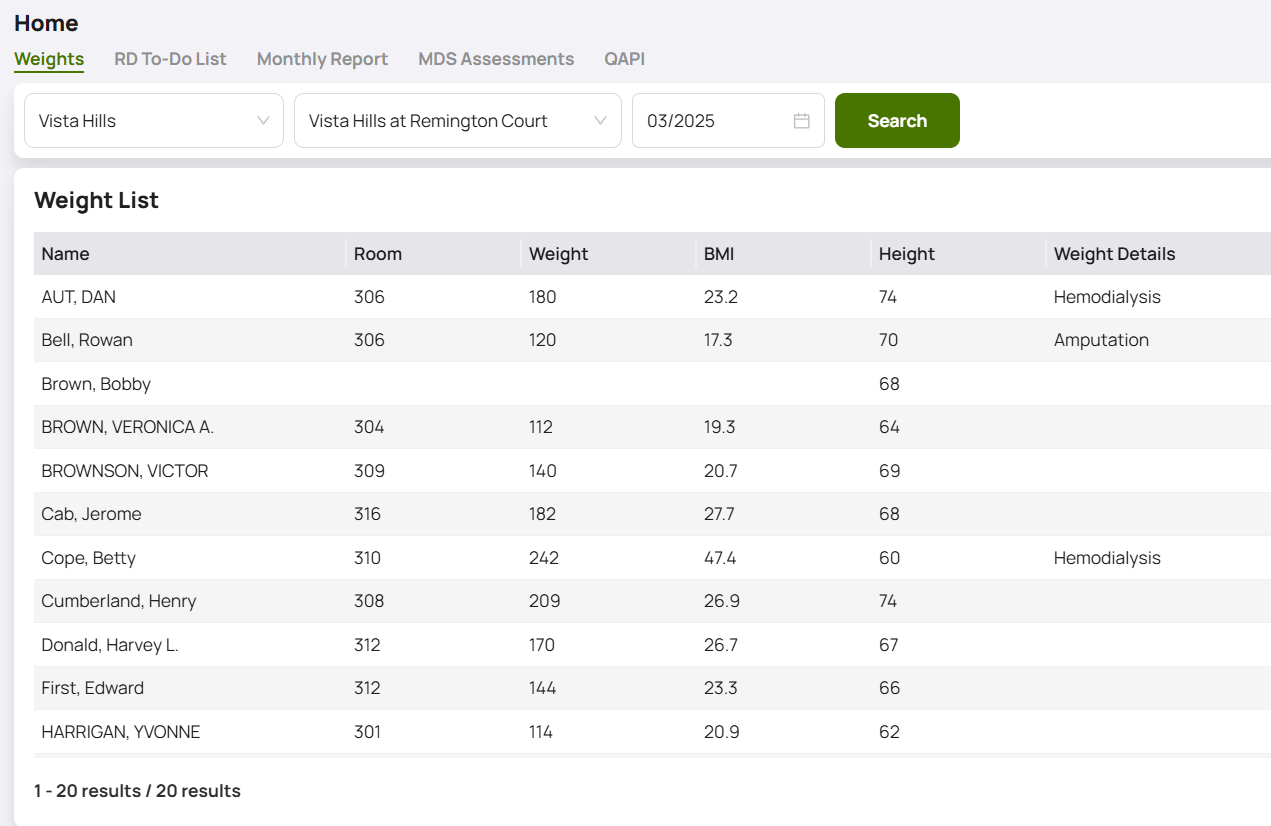

The most familiar method, where individuals manually input data through a user interface. This could be a staff member logging customer information, a field researcher inputting observations, or a loan officer entering applicant details.

Okay, so we have collected, stored and analyzed data. A lot of it. Good job! There does, however, remain one final, key step in the whole solution. We need to get the summations, metrics, and whatever analyses we have run, & present these to the end users – and these end users are almost certainly a mixed group of people. Some may have statistical and data knowledge. Most will not. Some may understand logarithmic graphs, histograms, box and whisker charts, but for many these widgest may only confuse the story. Choosing the right tools and visualizations are key in completing the data solution and presenting an understandable, lucid story to the interested parties.

Sometimes, the data is clear enough to the end users, that it simply needs to be presented in the right set of widgets. In a manufacturing context, the shop floor supervisor needs to see that the machinery is operating within acceptable tolerances. The saftey person needs to see that proper protocols are being observed, or that hazards are being avoided or tackled immediately. The inventory people need to see that the right amount of raw material is coming in and getting stored in the right places, and that the right amount of product is headed out the door.